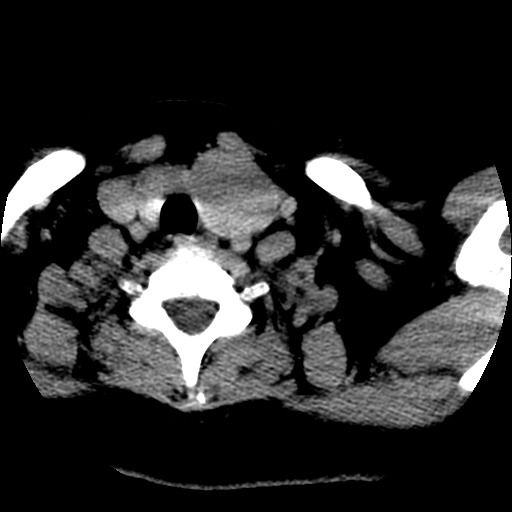

标题: CT25491:女,55岁,发现左侧甲状腺肿块一个月。 [打印本页]

标题: CT25491:女,55岁,发现左侧甲状腺肿块一个月。

女,55岁,发现左侧甲状腺肿块一个月,彩超示:甲状腺多发结节伴左叶结节液化。

左右叶都有,峡部也受累,有钙化,考虑结甲可能性大。

考虑右叶结节性甲状腺肿,伴左叶钙化。主要(1)密度均匀,边境清。(2)病灶与血管界限清。